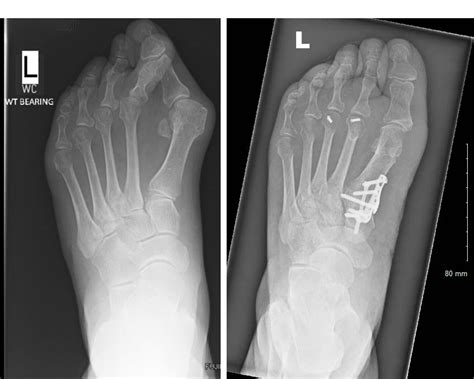

A clinical look at a Bunion X Ray showing bone misalignment

• Surgical Planning: If surgery is required, the X-ray acts as a blueprint to determine which type of osteotomy or fusion is necessary.

• Measuring the Angle: Doctors measure the Hallux Valgus Angle (HVA) and the Intermetatarsal Angle (IMA) to quantify the severity of the bunion.

• Joint Health: Identifying cartilage loss or the presence of bone spurs within the joint space.